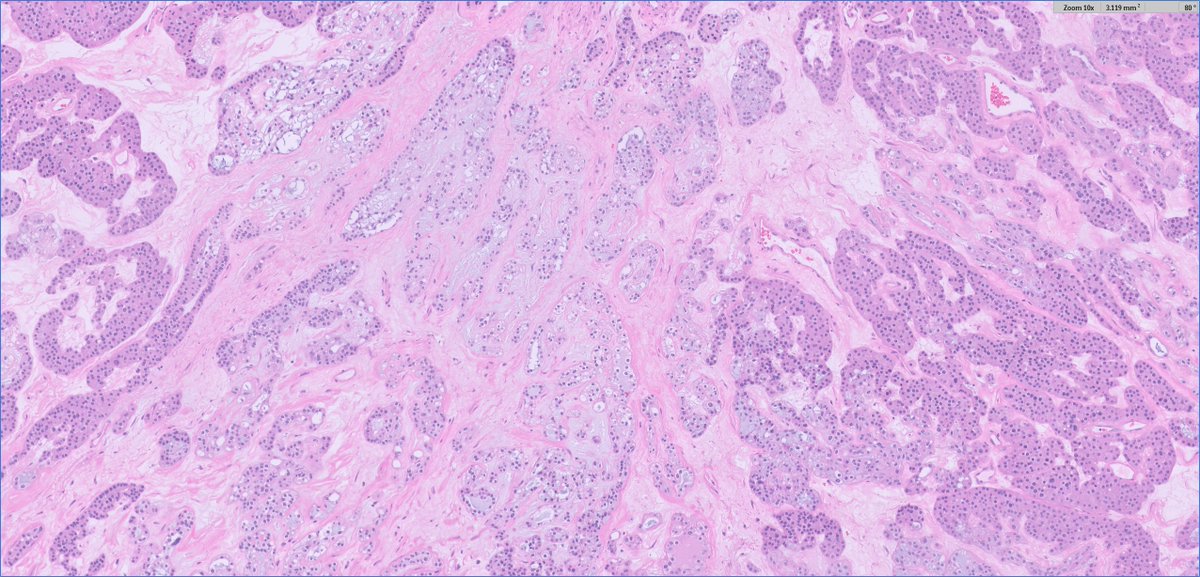

Placental Site Trophoblastic Tumor • RARE malignant trophoblastic neoplasm from intermediate trophoblasts • Mean Age: 31 • 2/3 cases follow full term pregnancy (median latency 12-18 months) • 🩺: Vaginal 🩸, uterine enlargement • ~25-30% may develop recurrent dz